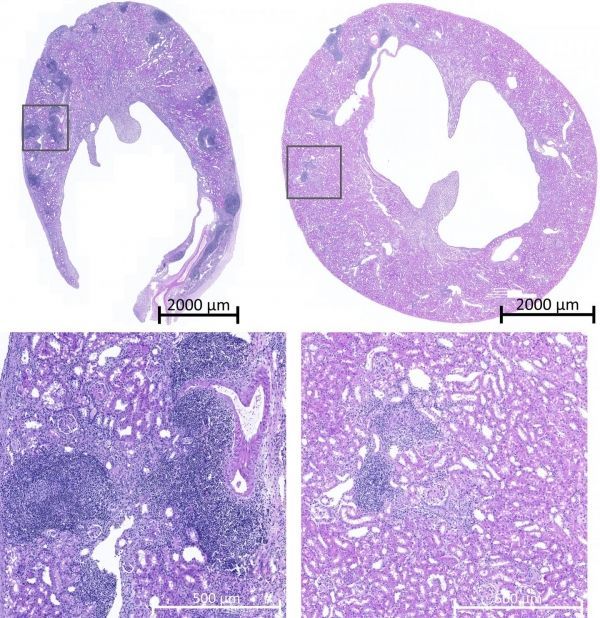

Image: Image of transplanted mouse kidney tissues showing recipient immune cells (blue) in normal (left) but not genetically modified mice (right). (Credit: Image adapted from Dai H et al., Science (2020))